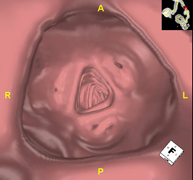

La colonoscòpia virtual és una tècnica no invasiva que permet la visualització tridimensional i bidimensional de l'intestí gros o del còlon mitjançant la presa seqüencial d'imatges captades amb TC Multidetector d'última generació. La qualitat de les imatges permet la navegació virtual per l'interior del recte i del còlon gràcies al processament en estacions de treball especialitzades. La preparació de la prova consisteix en realitzar una dieta baixa en fibra tres dies abans de la prova (per netejar el còlon i el recte) i de la ingesta de contrast oral iodat el dia abans de la prova (per marcar les femtes i poder distingir-les correctament de les possibles lesions colòniques). A diferència de la fibrocolonoscòpia, no requereix sedació ni solucions evacuants. La prova es realitza a la sala del TC, on, a través d'un petit tub flexible, s'insufla aire per distendre el còlon. - PAAF (Punció) Abdominal guiada per TC